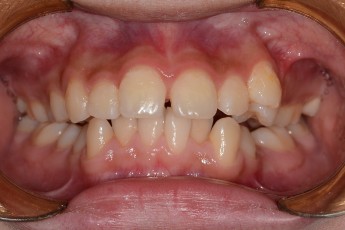

BEFORE & AFTER

- 반대교합교정